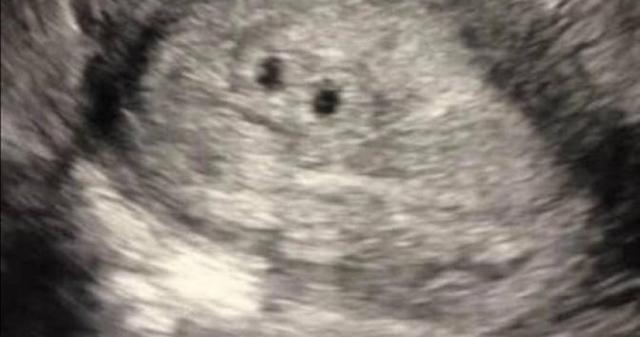

照顧孩子需要花相當大的精力與時間,如果爸爸不是神隊友都是媽媽在支撐,恐怕會出現嚴重家庭問題,日本有一名30歲女子因為不孕症無法懷孕,最後透過試管成功懷上3胞胎,但是生下孩子後卻開始了地獄生活。